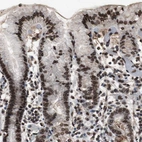

Immunohistochemical staining of human skin shows strong positivity in nuclear membrane in squamous epithelial cells.